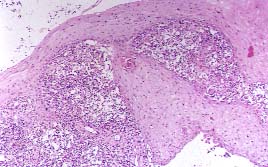

VIII. CROMOBLASTOMICOSIS

La Cromoblastomicosis, micosis verrucosa crónica de evolución muy lenta y que suele afectar preferentemente a los miembros inferiores (Fig.20), está producida por hongos pigmentados de la familia de los Dematiáceos. Suele acompañarse de hiperplasia seudoepiteliomatosa y formar microabscesos intraepidérmicos (Fig.21) y granulomas. En las zonas supuradas o en el interior de las celulas gigantes, libres, se observan los elementos característicos de la fase tisular de estos hongos, en forma de células esféricas, de 10 a 15 micras de diámetro, con pared de doble contorno y tabiques transversales, habitualmente dispuestos en grupos de 2 ó 3 elementos; son demominados "cuerpos fumagoides" (Fig. 22) o "formaciones en mórula" (13). Los agentes etiológicos viven saprofíticamente en la naturaleza, sobre todo en restos de vegetales, produciéndose su penetración a través de microtraumatismos producidos con espinas o astillas.

21p.jpg (22235 bytes)

Fig.21